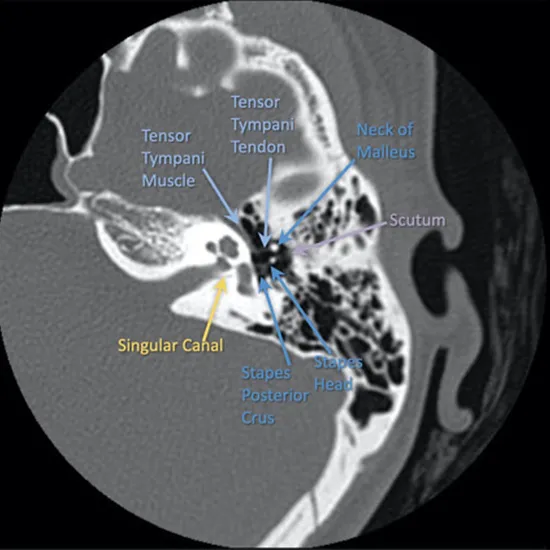

NCCT(Non-Contrast Computed Tomography) Head with Temporal Bone is an imaging procedure that provides detailed information about the brain structure and temporal bone. NCCT Head provides a detailed picture of the structure of the brain as well as its tissues. NCCT Temporal bone provides a detailed picture of the lower part of the skull and its surrounding tissues.